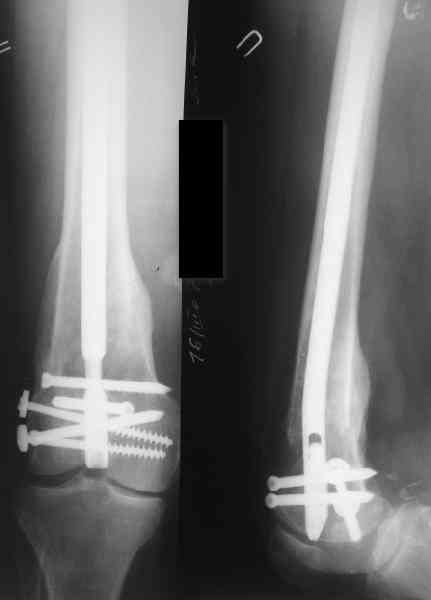

В приложении как раз видна эволюция использововшихся у нас большеберцовых гвоздей. Первый - дизайн как у UTN, второй - разнесены 45 градусные отверстия (зачем их вообще изначально так нелепо на одном уровне сделалм???), третий - убрано сиавшее лишним статическое отверстие, Herzog's bend перемещен более проксимально.

Забавненько смотрится... "век живи, век учись", как говорится. А чья мысль использовать блокируемые штифты для б/берцовой кости при переломах бедра? Такое встречалось где-то в литературе или это ваше ноу-хау?

Насколько я помню, мы использовали этот вариант после знакомства с гвоздями SIGN, которые вообще одинаковые для бедра и голени, и дизайн у них большеберцовый.